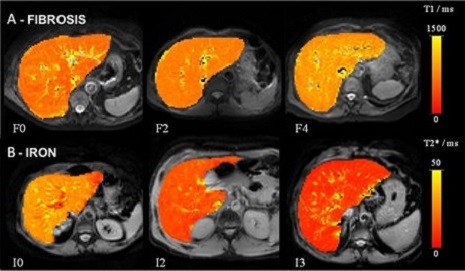

Examples of liver relaxometry

Examples of (left to right) liver relaxometry, kidney perfusion and imaging of food materials in the stomach Examples of (left to right) liver relaxometry, kidney perfusion and imaging of food materials in the stomach